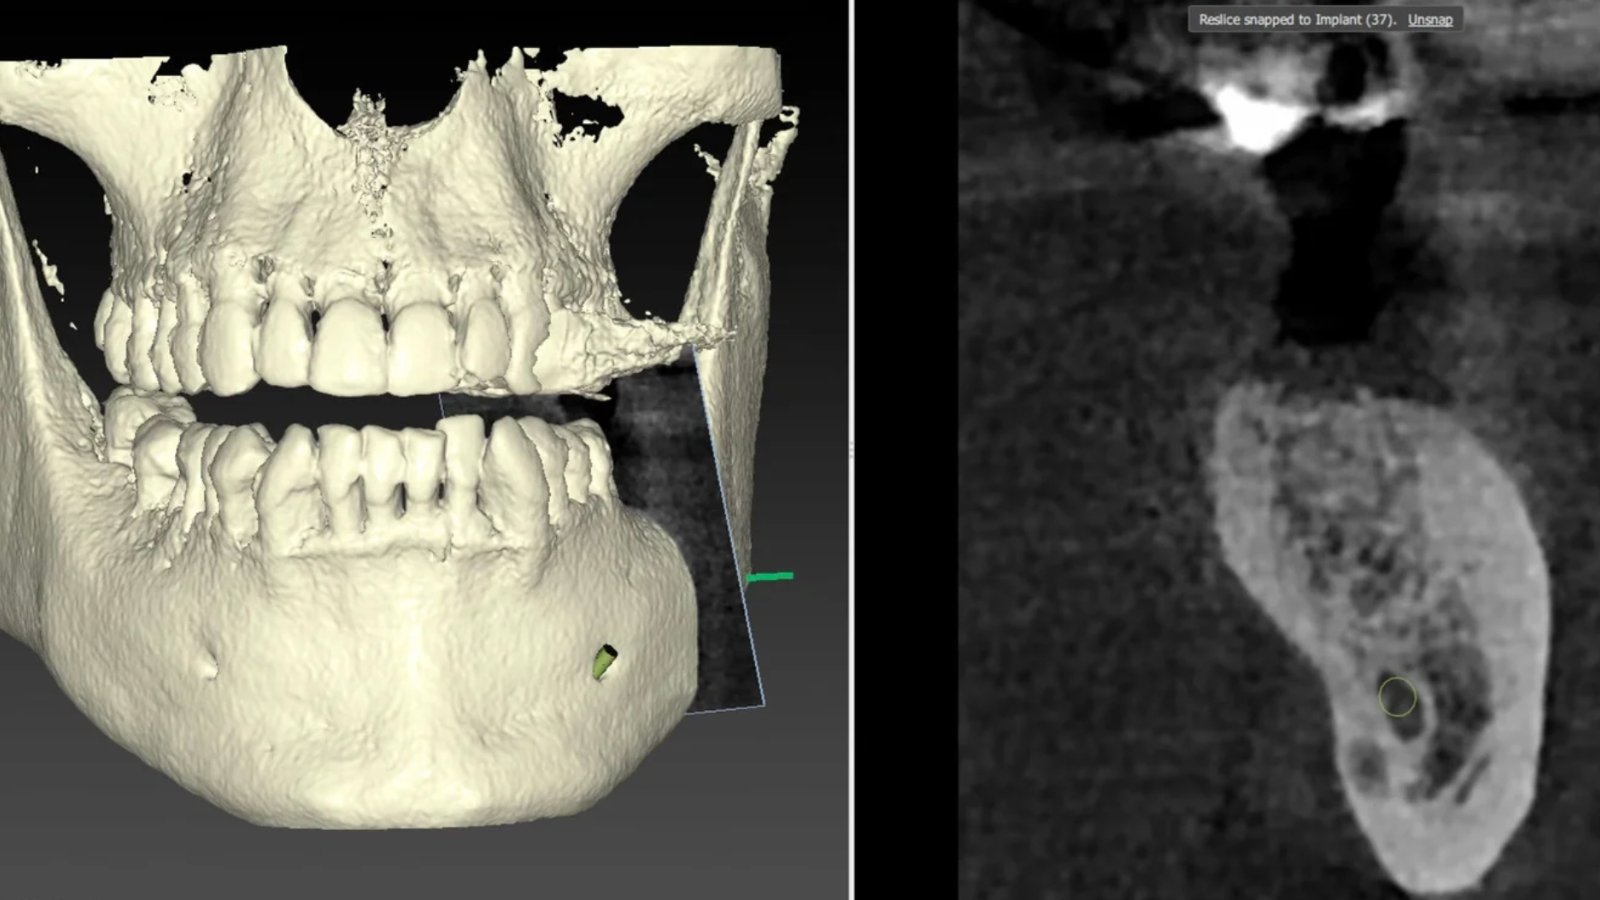

Greffes osseuses pour restaurer la structure dentaire

Lorsque l’os de la mâchoire est insuffisant pour supporter un implant ou entraîne un défaut esthétique, une greffe osseuse peut être réalisée.

• Greffe d’apposition : Un greffon osseux est ajouté sur une surface existante pour augmenter le volume osseux.

• Régénération osseuse guidée (ROG) : Une membrane est utilisée pour guider la régénération osseuse, protégeant le site de la greffe et optimisant la croissance de l’os.

Ces techniques peuvent être combinées pour maximiser les résultats, en fonction des besoins spécifiques du patient.